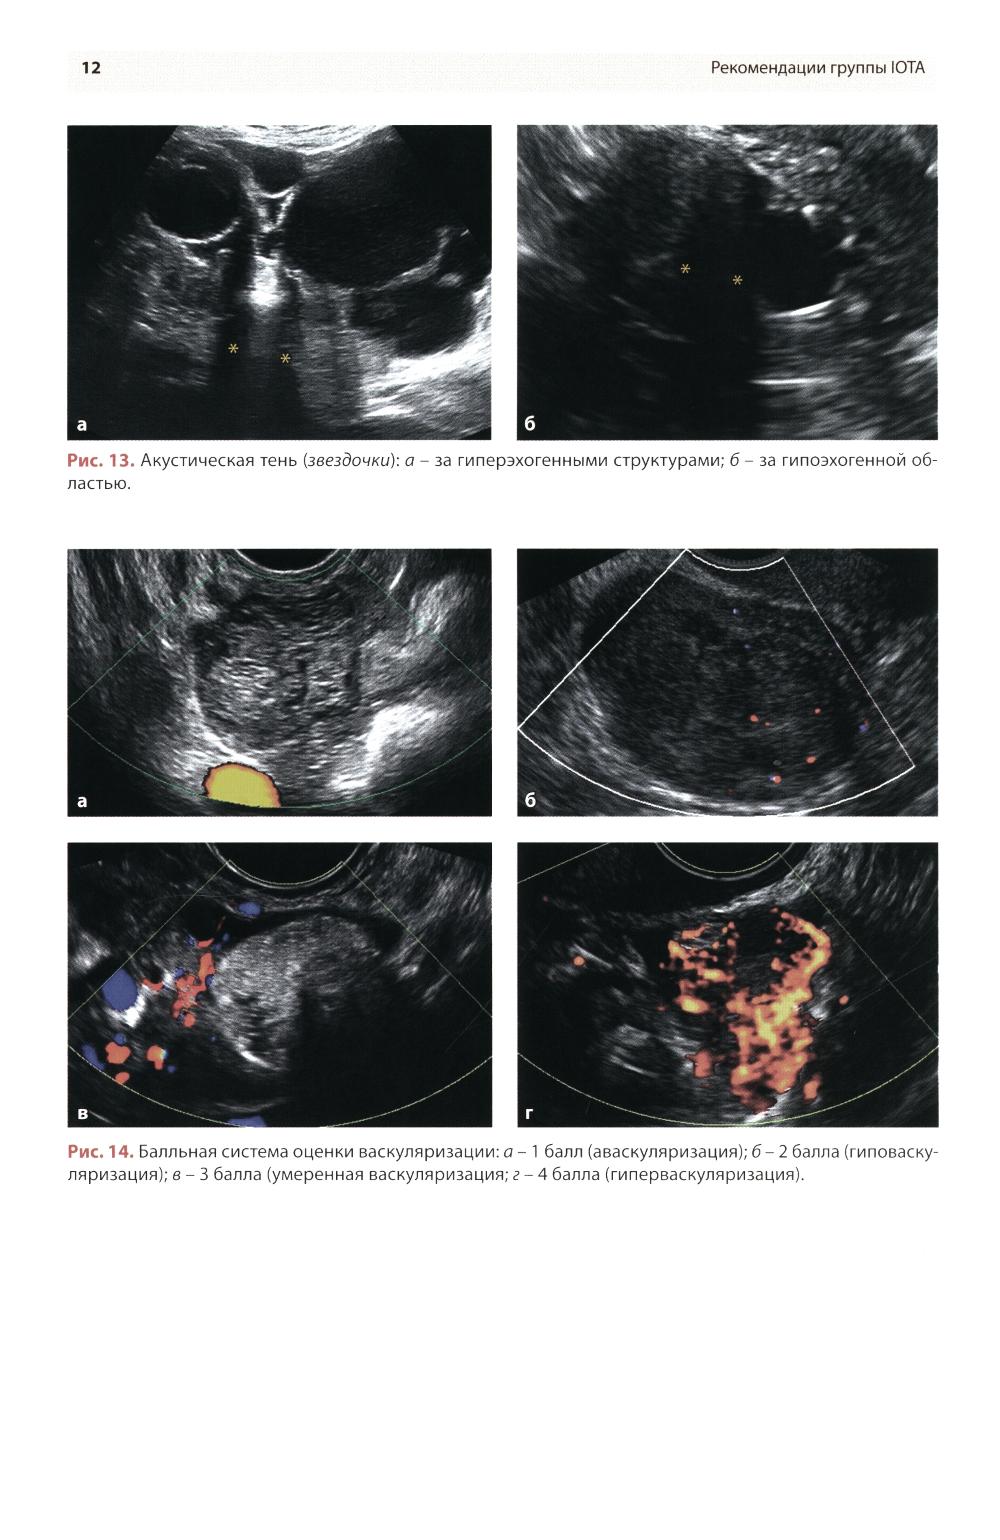

Методические рекомендации по стандартизации ультразвукового исследования с целью своевременной диагностики опухолевого процесса. Книга также включает вопросы дифференциальной диагностики физиологических изменений яичников, опухолевидных и опухолевых заболеваний и маршрутизации пациенток. Утверждено в качестве методических рекомендаций для проведения циклов первичной переподготовки врачей по ультразвуковой диагностике, тематического усовершенствования «Ультразвуковая диагностика в гинекологии», общего усовершенствования, ординаторов и аспирантов, проходящих обучение по направлению «Ультразвуковая диагностика, акушерство и гинекология».| Издательство | МЕДпресс-информ |